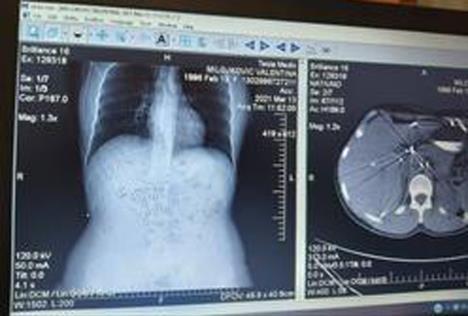

Jedna sam u milion koja je preživela ovako teško ranjavanje. Operisano mi je 12 organa, imam 30 odsto pankreasa, jetra mi je povređena, nemam četiri rebra i nosim dve kese, aorta mi je krpljena titanijumskim kopčama. Ipak, uz božju pomoć, a zbog mog sina, preživela sam.

- Pošto me je upucao olovom, ostalo mi je 80 dramlija u stomaku. Počela sam da radim, funkcionišem relativno normalno, ali mi pankreas slabi svake godine. Da bih nastavila normalan život, moram da se podvrgnem trećoj operaciji, da probaju da mi izvade dramlije. Mnogo sam zahvalna divnom timu lekara koji me je spasao - kaže Valentina.